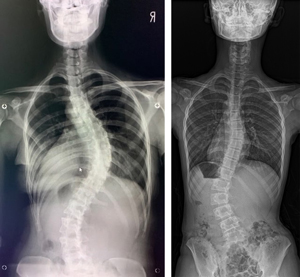

せぼね(脊椎)は7個の頚椎、12個の胸椎、5個の腰椎と仙椎から構成されます。正常な状態では脊椎は正面から見ると真っ直ぐです。一方側弯症では正面から見た時に椎体がねじれ(回旋)を伴いながら、脊椎が左右に曲がっている状態です。

3-12ヶ月毎にX線を撮影して側弯の進行を確認します。このような場合はカーブの大きさがコブ角(カーブしている椎体の上の端と下の端を直線で延ばして交わる角度)で25度以下の軽度の側弯症の場合です。